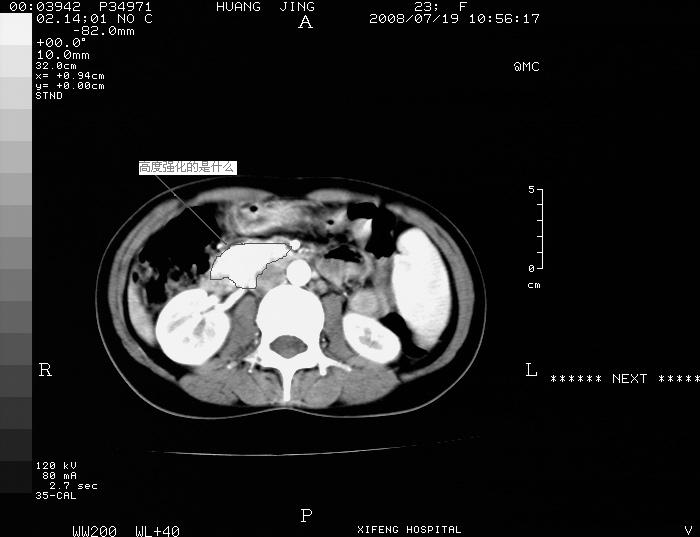

f 33y  b超发现胆囊结石,不是发现胆总管对石。请大家看一下,腔静脉右前方强化和主动脉差不多不规则区域是什么。谢谢